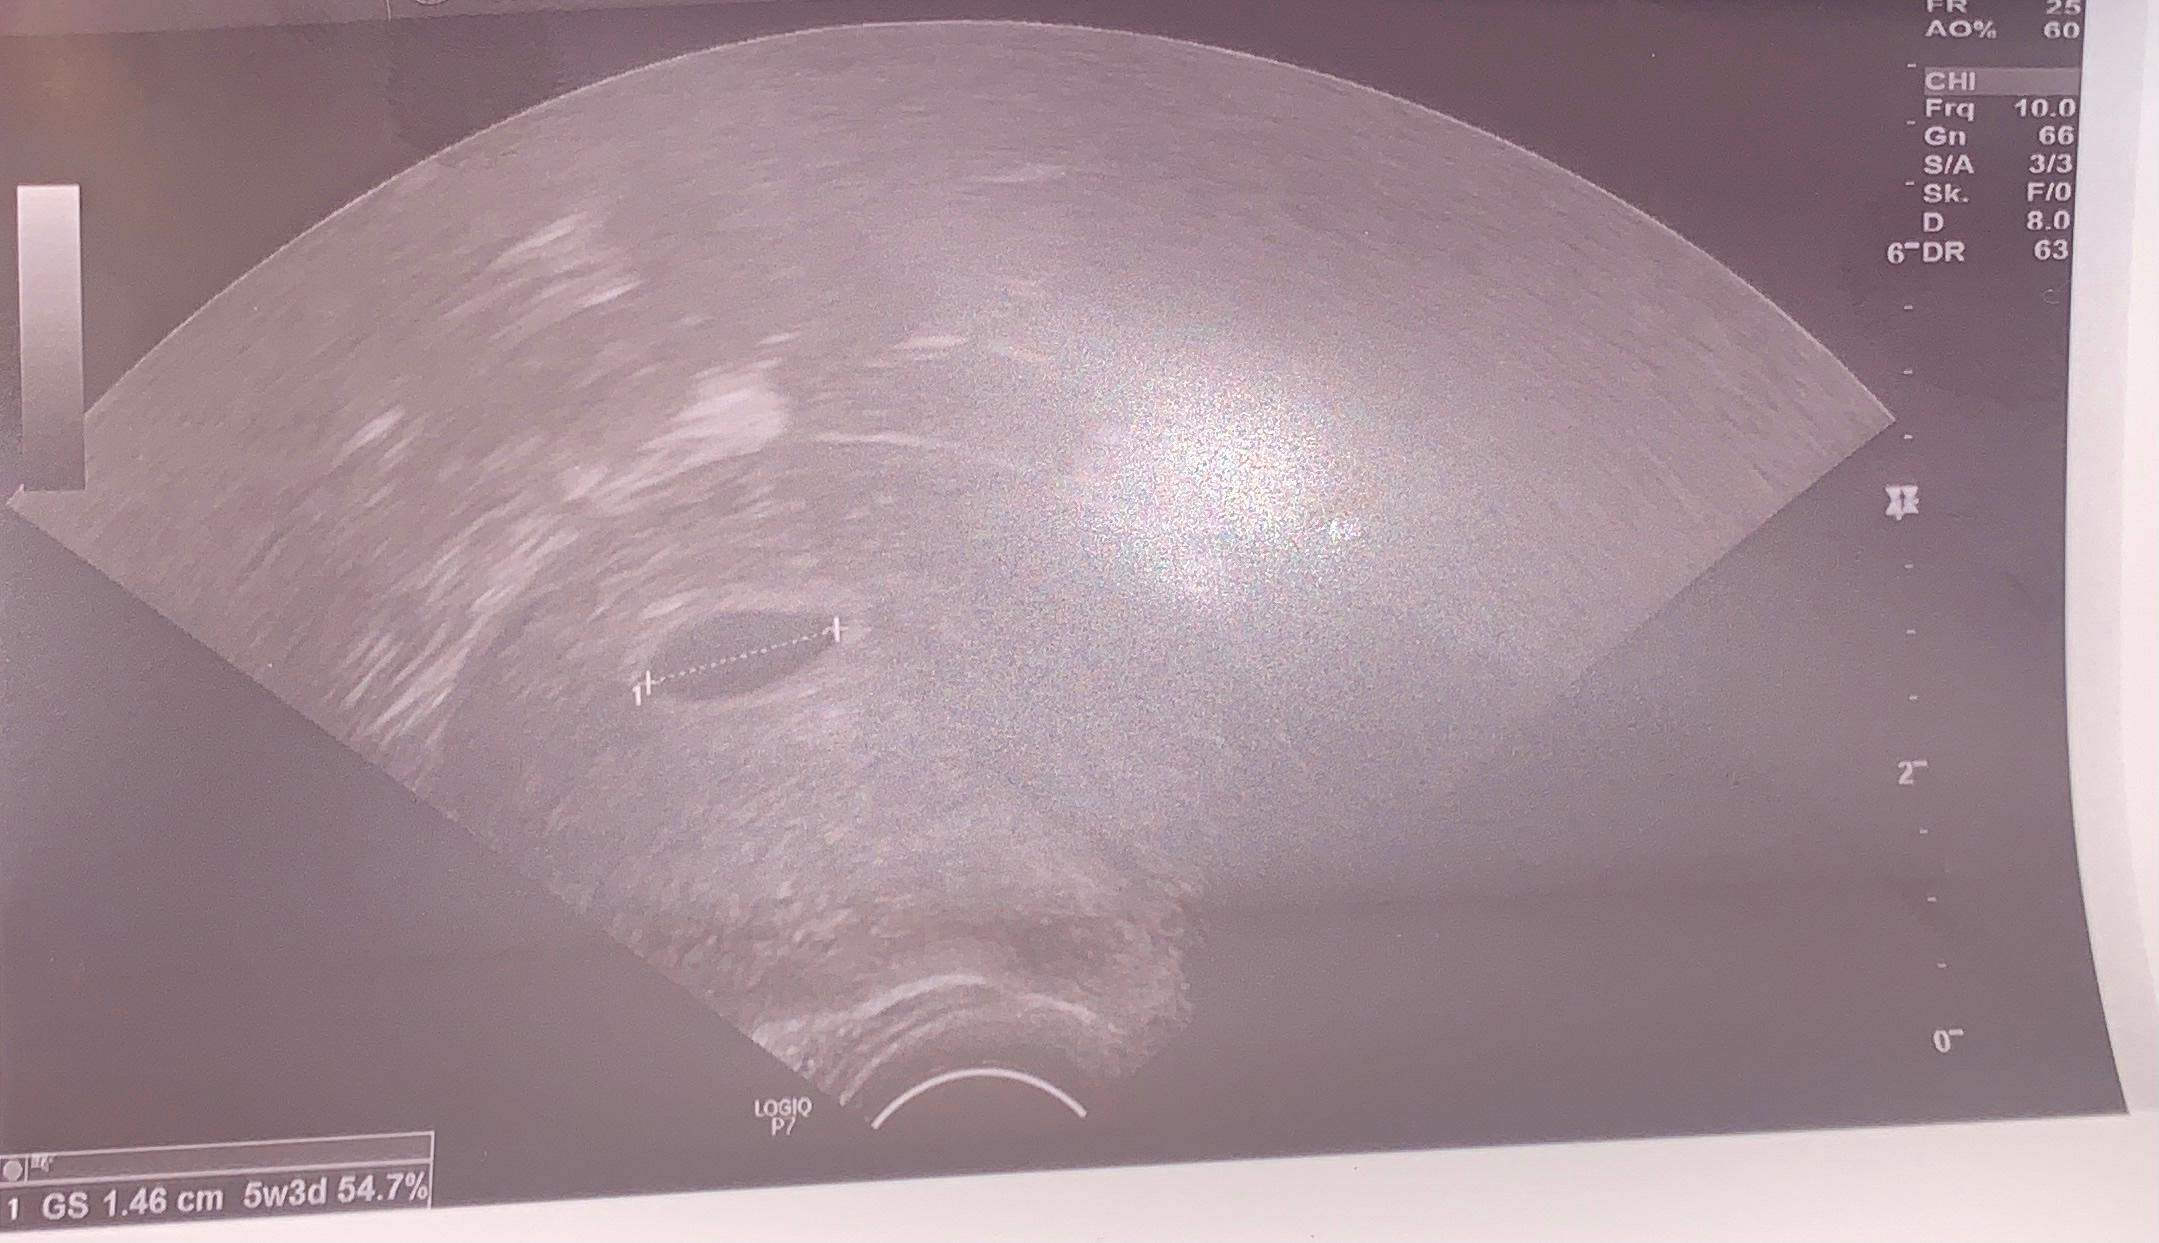

7 Ssw Kein Embryo Zu Sehen Aber Dottersack

7. Schwangerschaftswoche. Sieben verdammt lange Tage mal sieben. Und was sehen wir beim Ultraschall? Einen Dottersack. Ja, super. Einen Dottersack. Nicht, dass ich ihn nicht zu schätzen wüsste, den kleinen, gelblichen Retter in der Not. Aber ehrlich? Ich will ein Embryo sehen! Am besten schon mit Mini-Ärmchen und Beinchen, die wild strampeln. Ist das zu viel verlangt?

Ich weiß, ich weiß. Der Dottersack ist wichtig. Er nährt das Baby in spe, bevor die Plazenta ihren Job übernimmt. Er ist ein kleines Wunderwerk der Natur. Aber ganz ehrlich? Er ist auch ein bisschen langweilig. Er sieht aus wie ein Spiegelei, das in einem Mini-Aquarium schwimmt. Und ich bin hier, um BABYFOTOS zu sehen, nicht Eier!

Das Internet ist voll von beruhigenden Artikeln. "7. Woche und nur Dottersack? Keine Panik!" "Späte Einnistung? Alles im grünen Bereich!" Ich liebe ja Optimismus. Aber wenn ich innerlich schon die Geburtsanzeigen entwerfe und mir Namen ausdenke, dann möchte ich auch Beweise dafür haben, dass da tatsächlich jemand wohnt! Der Dottersack allein überzeugt mich da leider nicht ganz. Er ist wie die leere Pizzaschachtel nach einer Party. Ein Indiz, ja. Aber wo ist die Pizza, bitte?

Natürlich ist da immer dieses kleine "Was, wenn…?" im Hinterkopf. Was, wenn es doch nicht geklappt hat? Was, wenn es eine Fehlgeburt wird? Diese Ängste sind normal. Aber ich versuche, sie zu verdrängen. Denn Panik hilft jetzt auch nicht weiter. Lieber konzentriere ich mich auf die positiven Dinge: Ich bin schwanger. Ich habe einen Dottersack (ja, ich gebe es zu, er ist wichtig). Und in ein paar Wochen werde ich hoffentlich einen kleinen, strampelnden Mensch auf dem Ultraschall sehen. Bis dahin übe ich mich in Geduld. Und schimpfe heimlich über Dottersäcke.